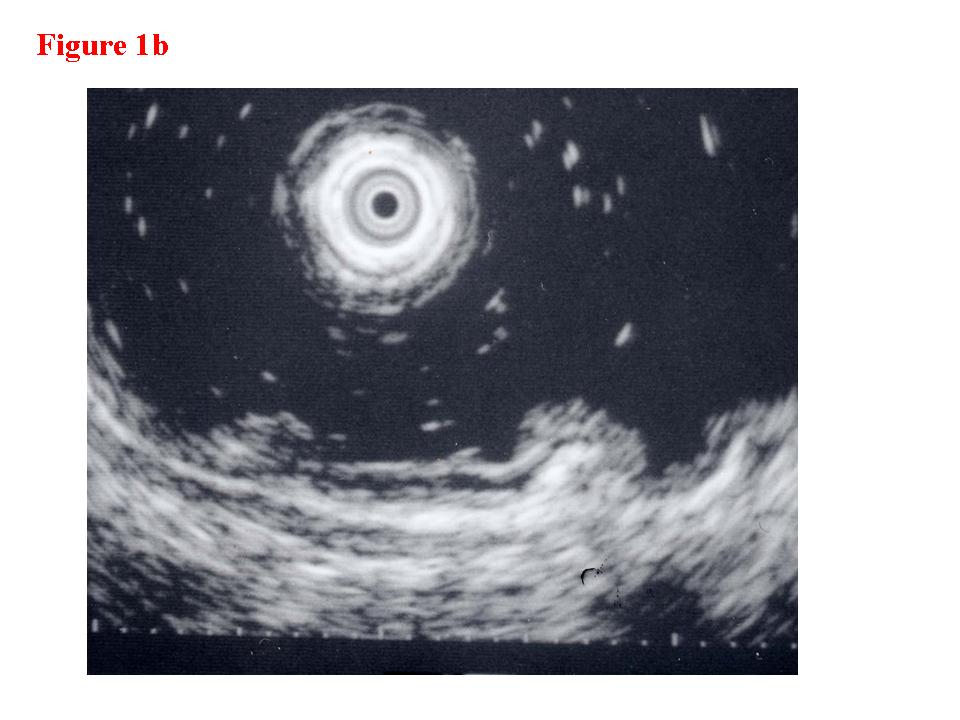

Figure 3.  Early colon cancer lesion (EUS-SM). a) Endoscopic features of superficial depressed type early colon cancer lesion.  b) The depth of the change for the third layer (submucosal layer) is more than 1 millimeter. EUS finding is EUS-SM.  Surgical operation was recommended. c) The patient once refused surgical operation and chose palliative EMR.  d) Pathological result of EMR specimen is SM deep invasion over 1 millimeter.  With this information, the patient’s mind changed and an additional surgical operation was performed.